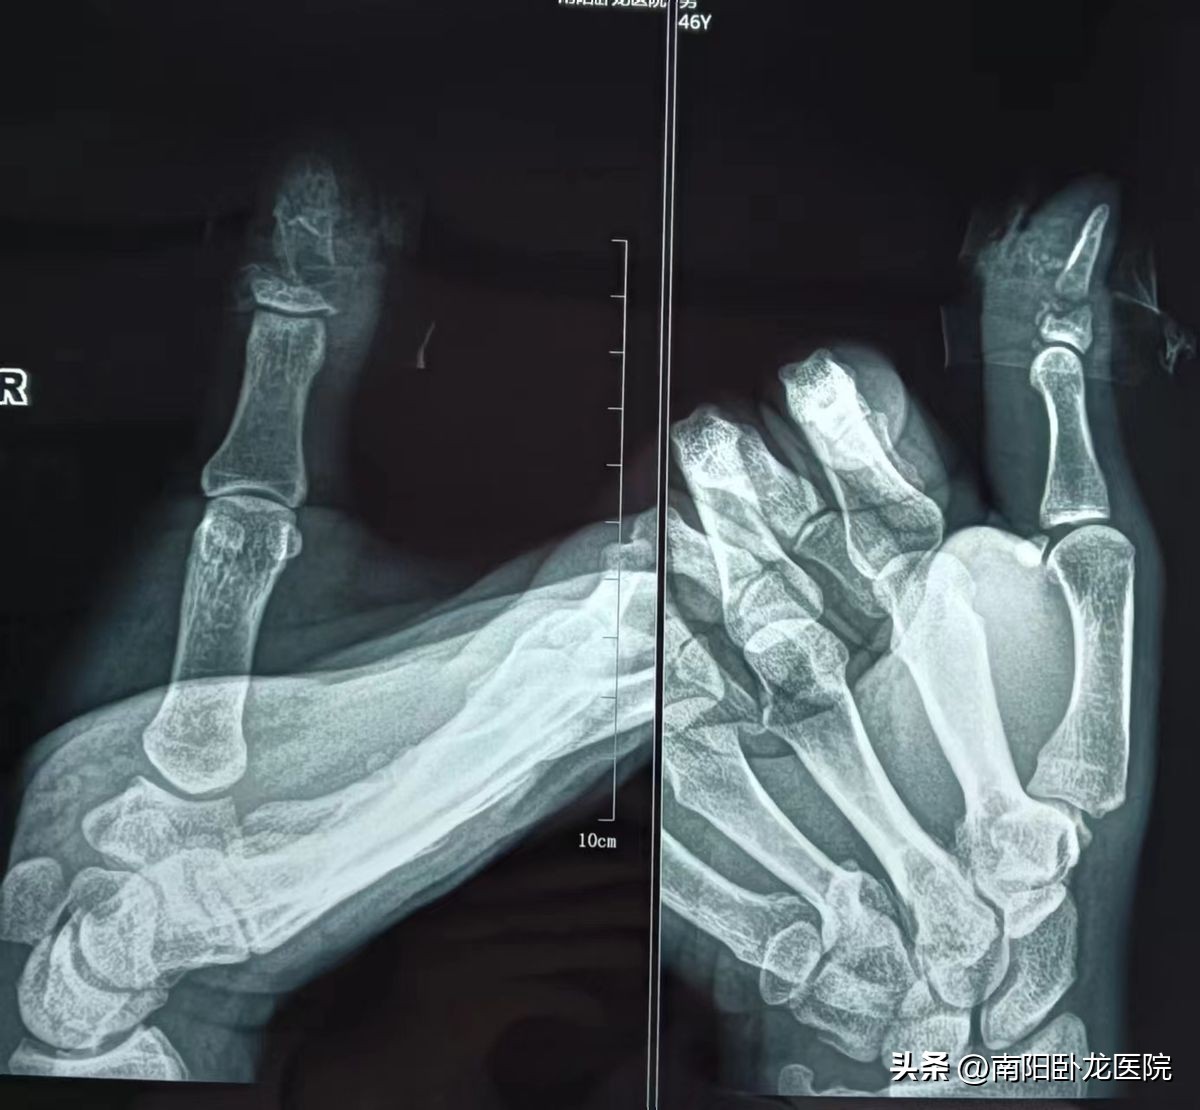

患者锯伤后右手拇指不完离断,仅有少许皮肤及伸肌腱相连,电锯致右手拇指骨及软组织缺损。我院创伤中心,骨外科开启绿色通道急诊行断指再植术。显微镜下清创后,去除部份指骨,克氏针固定复位骨折。在显微镜下探查动脉,尺侧动脉完完缺失,桡侧指固有动脉直径仅仅只有约0.3毫米,用比眼睫毛还小的针与比发丝还细的11-0无损伤缝合线,在高倍显微镜下,吻合指动脉,间断缝合指体。术后给予抗炎,抗凝,抗血管痉挛,红外线理疗,最终取得胜利。